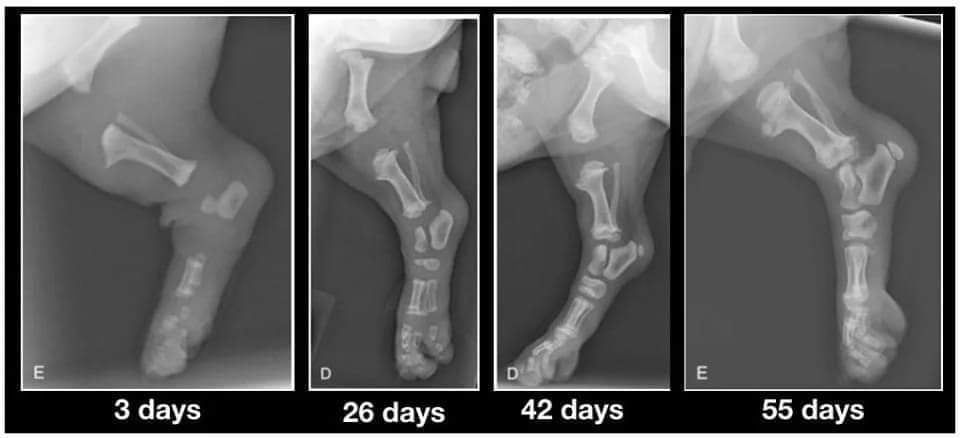

Lorsque vous accueillez votre chiot entre 8 et 12 semaines, ayez ces images à l'esprit, ses os ne touchent pas encore. S’il se déplace si maladroitement avec ses grosses pattes et ses mouvements bancals c’est parce que ses articulations sont entièrement constituées de muscles, de tendons, de ligaments, son squelette n’est « pas soudé ».

Photos Veteriankey.com @ 62 jours

L'ossification endochondrale (le processus durant lequel le cartilage se transforme en os), diffère selon la taille adulte du chiot. L’ossification complète avec fermeture des plaques de croissance se produit entre 3 mois dans les races de mini et 24 mois dans les grandes races (voir photos) ...